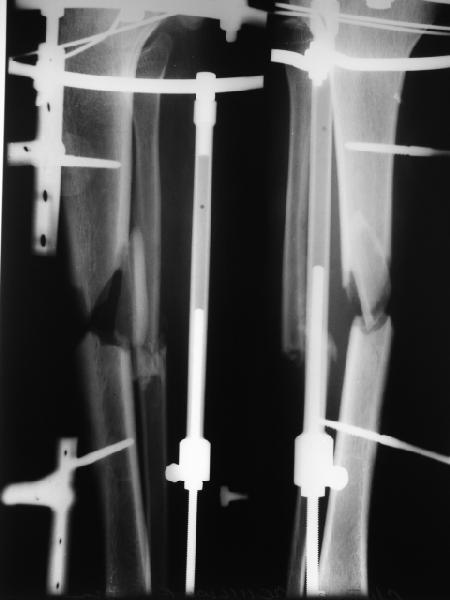

Вот пример, тоже открытый перелом, первичный дефект, пробыл в аппарате 5 мес. Титановый гвоздь,  сразу динамический, без покрытия. Больше не делали ничего.

Имя     : get_image1.jpg

Тип     : image/jpg

Размер  : 25191 байтов

Описание: отсутствует

Url     : http://weborto.net:8080/pipermail/ortho/attachments/20111023/02514467/attachment-0003.jpg